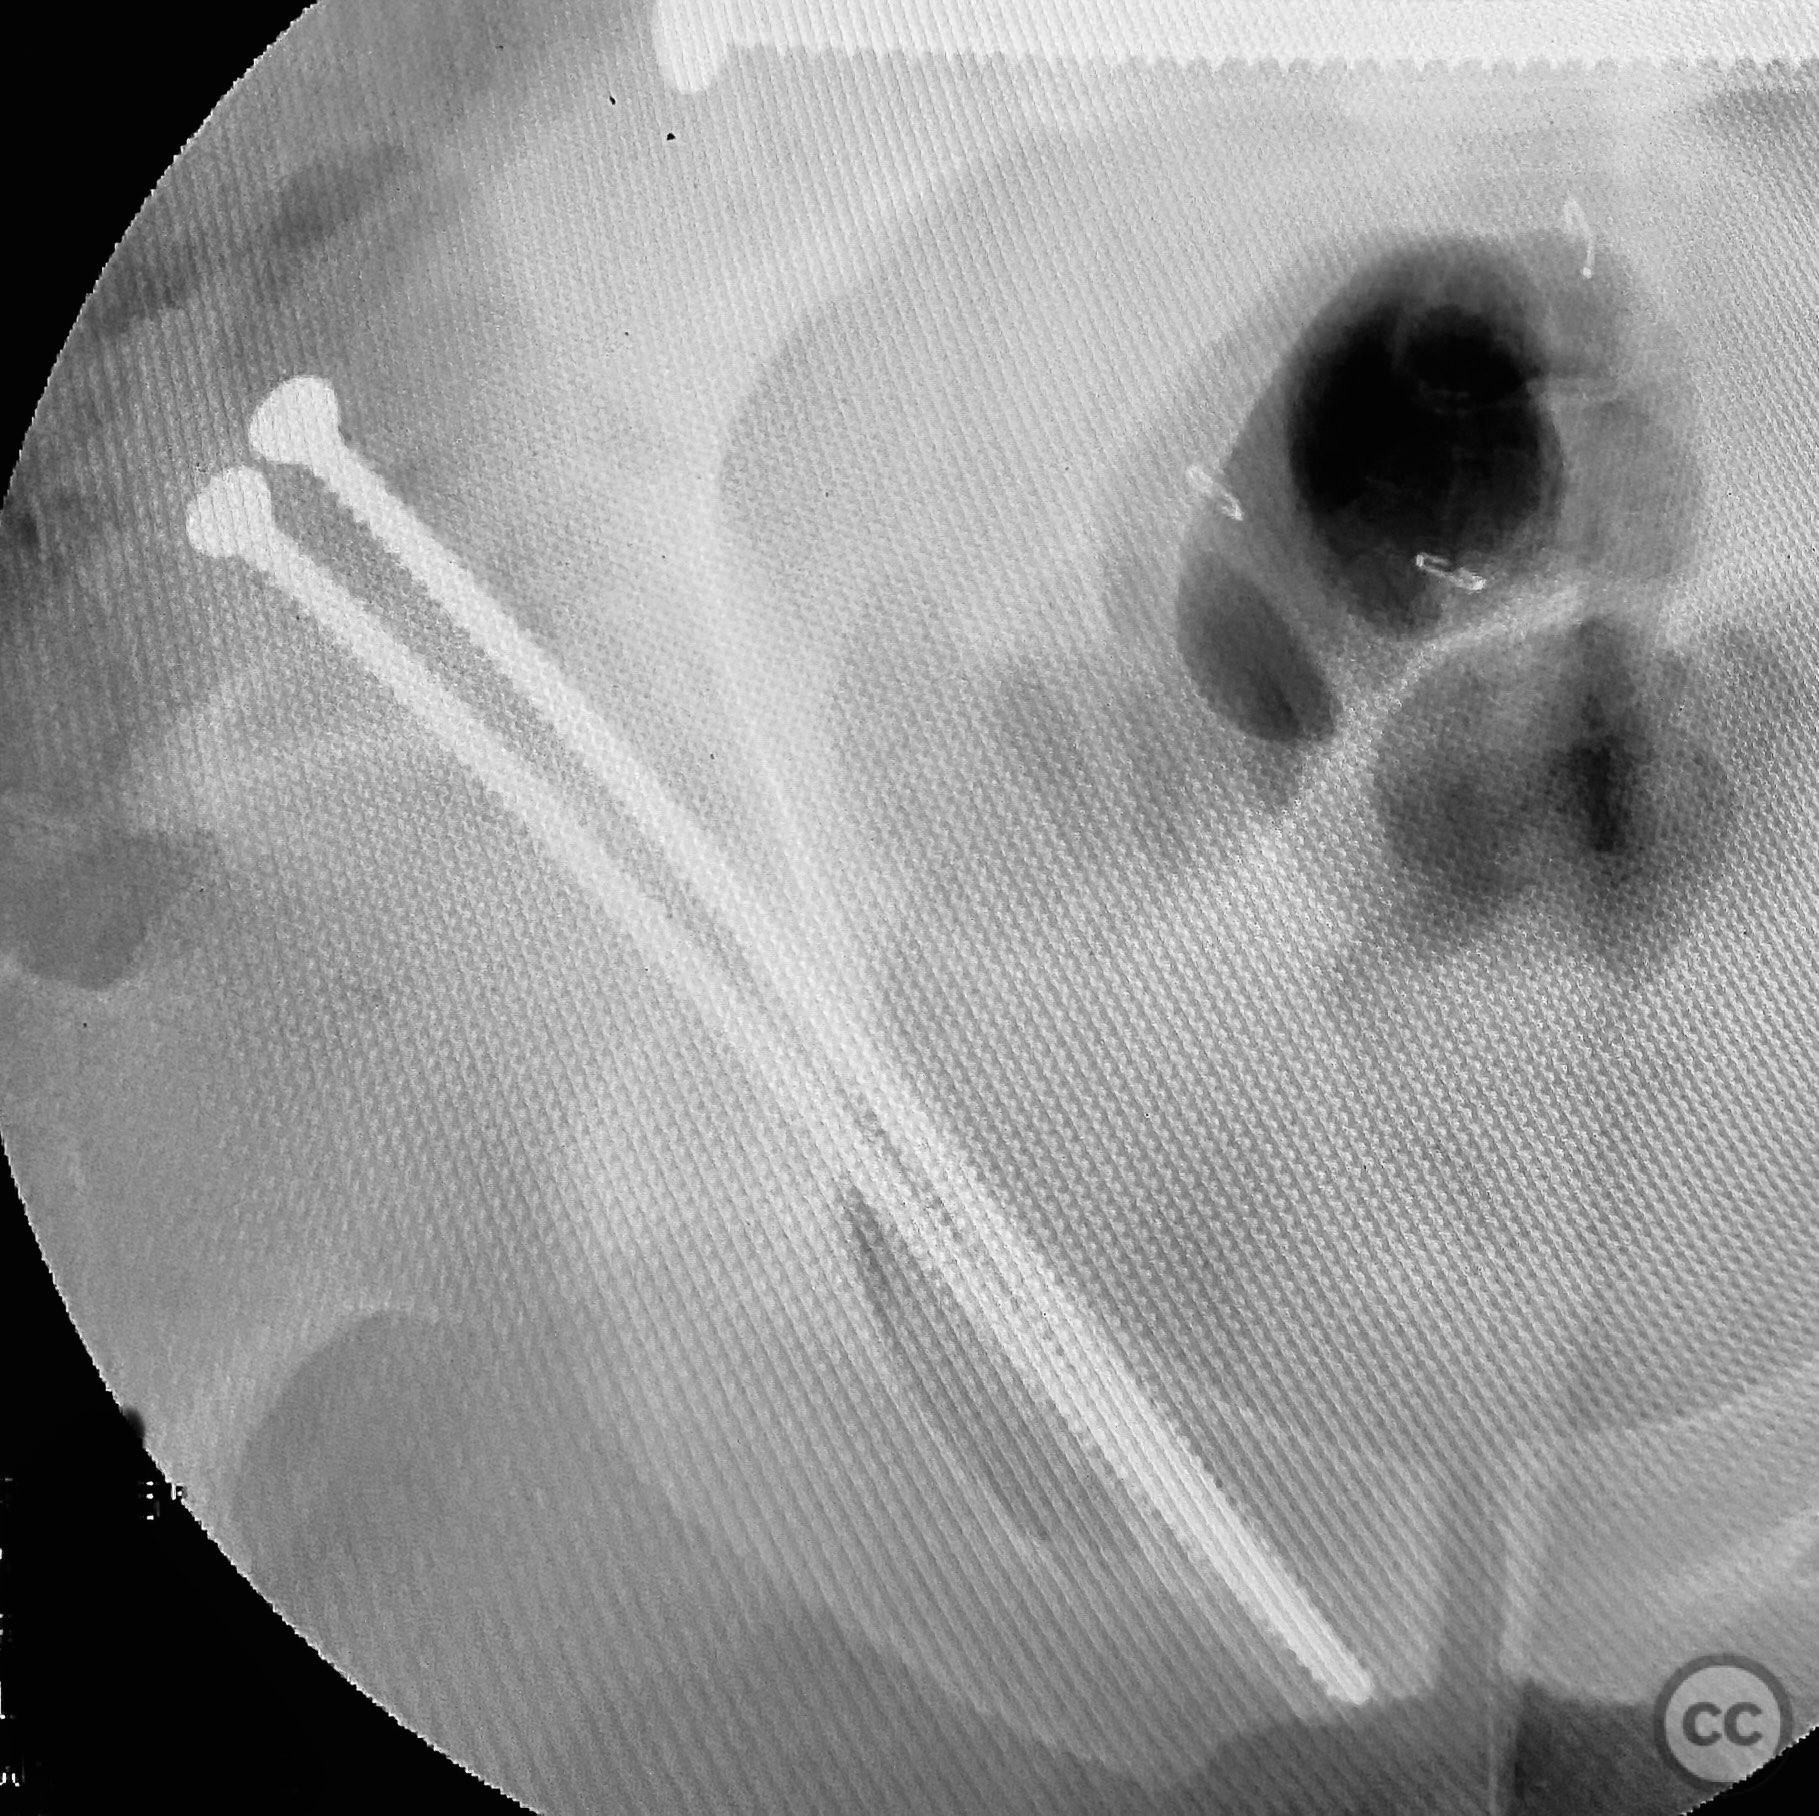

Clinical and radiological findings:  Adult male with a closed, comminuted left femoral shaft fracture and complex pelvic ring injury. Initial imaging demonstrated bilateral sacroiliac (SI) joint disruptions and a left-sided transtectal transverse acetabular fracture (Letournel-Judet: transverse type), with the fracture line exiting through the posterior wall region but without a discrete posterior wall fragment. The femoral head was displaced caudally, following the unstable distal acetabular segment, resulting in loss of congruency with the intact acetabular dome. There was also a symphyseal disruption. No associated abdominal, visceral, thoracic, cranial, or other injuries were present. Application of a circumferential pelvic binder resulted in visible changes in pelvic alignment on imaging. AO/OTA Classification: - Pelvic ring: 61-C1.3 (bilateral SI joint disruption, complete instability) - Acetabulum: 62-B1 (transverse fracture) - Femur: 32-C3 (comminuted diaphyseal fracture)

Operative remarks:

Initial reduction of the posterior column was attempted using a Jungbluth clamp; however, intraoperative fluoroscopy revealed suboptimal reduction despite satisfactory direct visualization. A perpendicular reduction clamp was then applied, resulting in improved alignment as confirmed by fluoroscopy. The transverse acetabular fracture was stabilized with two 4.5 mm cortical screws placed across the fracture line, followed by application of posterior column plates for additional stability. The symphyseal disruption was managed non-operatively without direct stabilization.